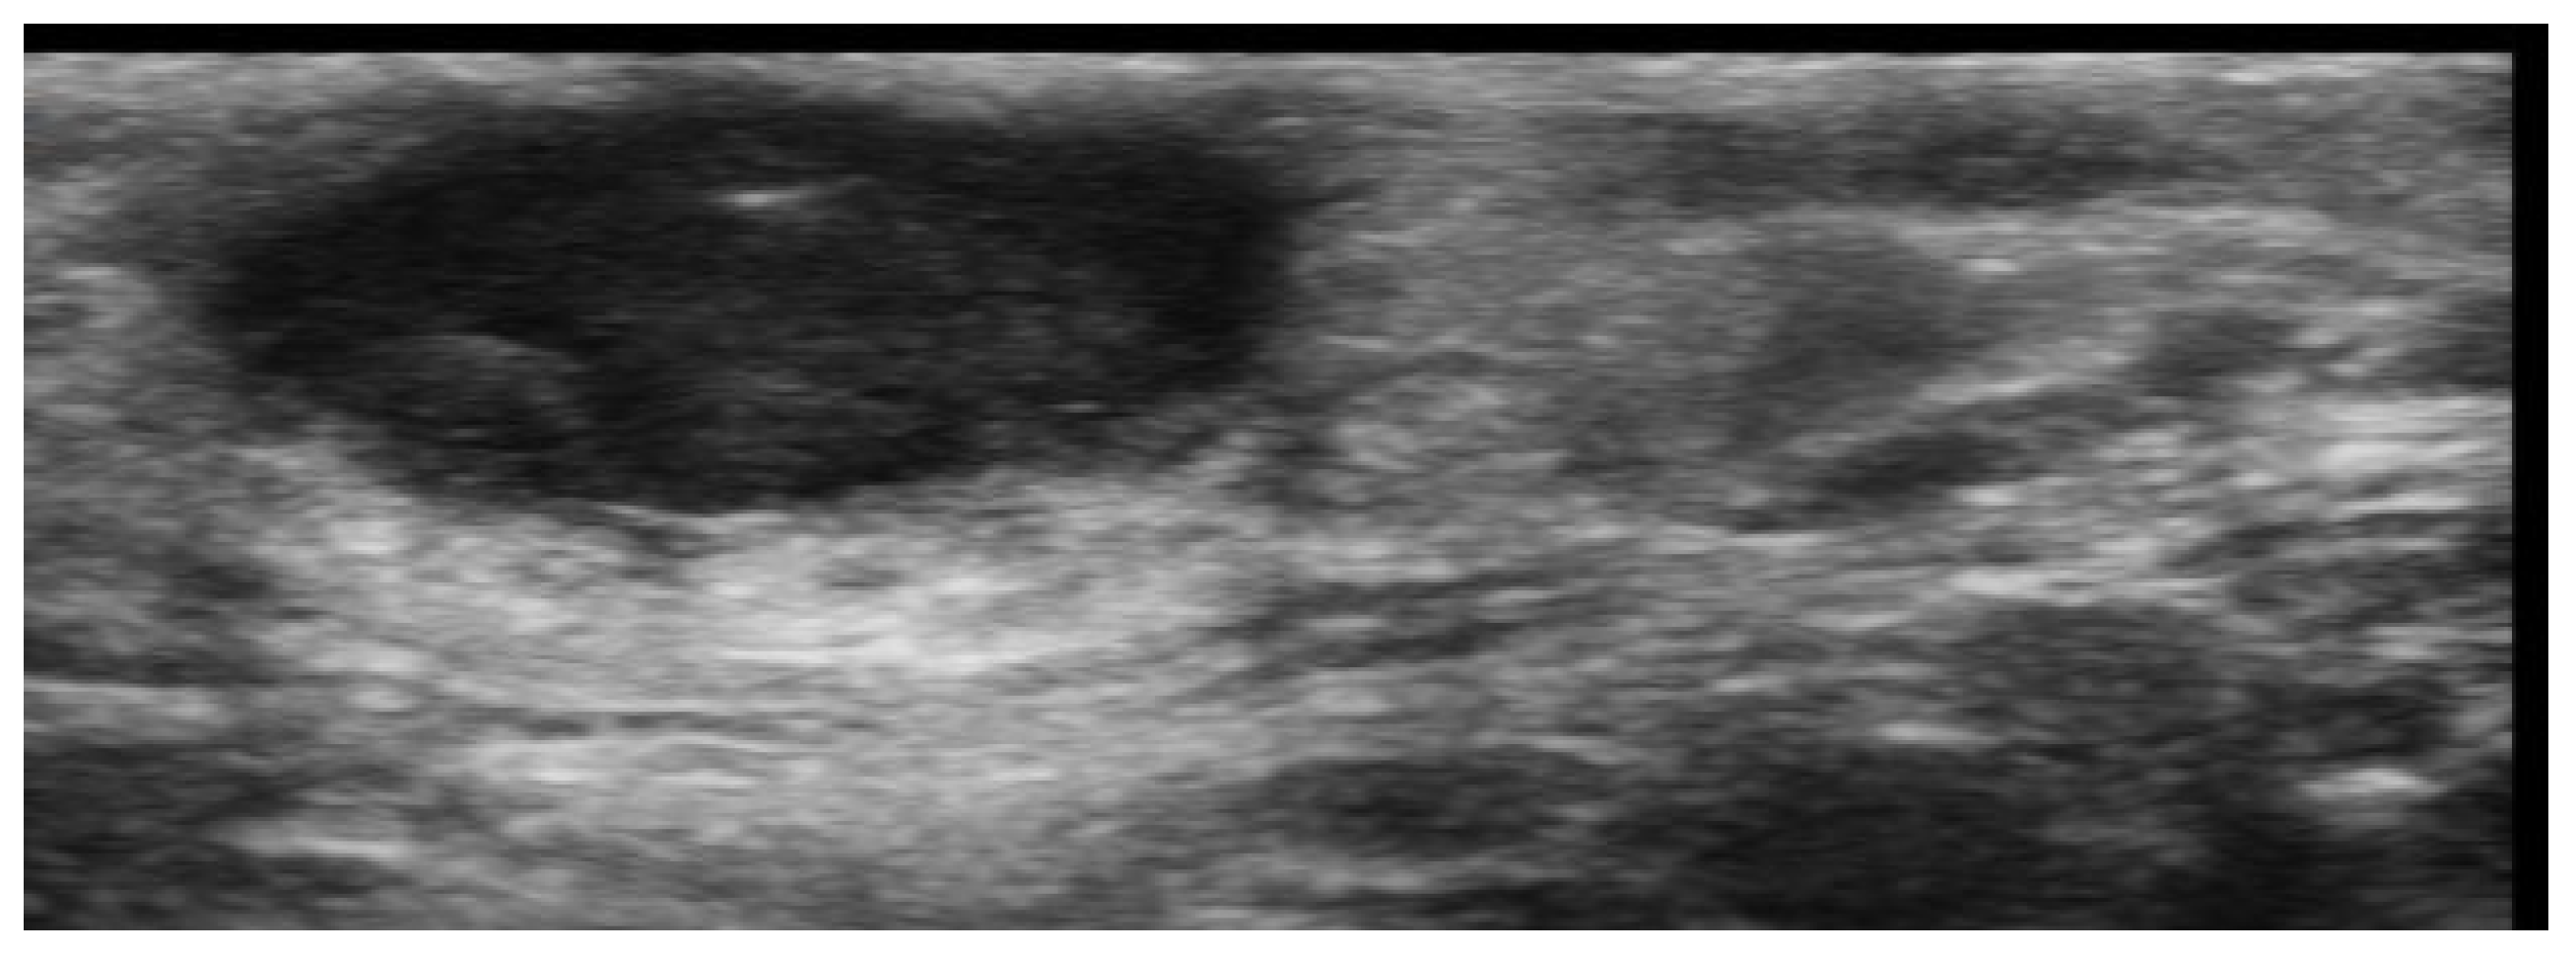

- Wortsman, X. Update on Ultrasound Diagnostic Criteria and New Ultrasound Severity and Activity Scorings of Hidradenitis Suppurativa: Modified SOS-HS and US-HSA. J. Ultrasound Med. 2024, 43, 207–213. [Google Scholar] [CrossRef] [PubMed]

- Mendes-Bastos, P.; Martorell, A.; Bettoli, V.; Matos, A.P.; Muscianisi, E.; Wortsman, X. The use of ultrasound and magnetic resonance imaging in the management of hidradenitis suppurativa: A narrative review. Br. J. Dermatol. 2023, 188, 591–600. [Google Scholar] [CrossRef]